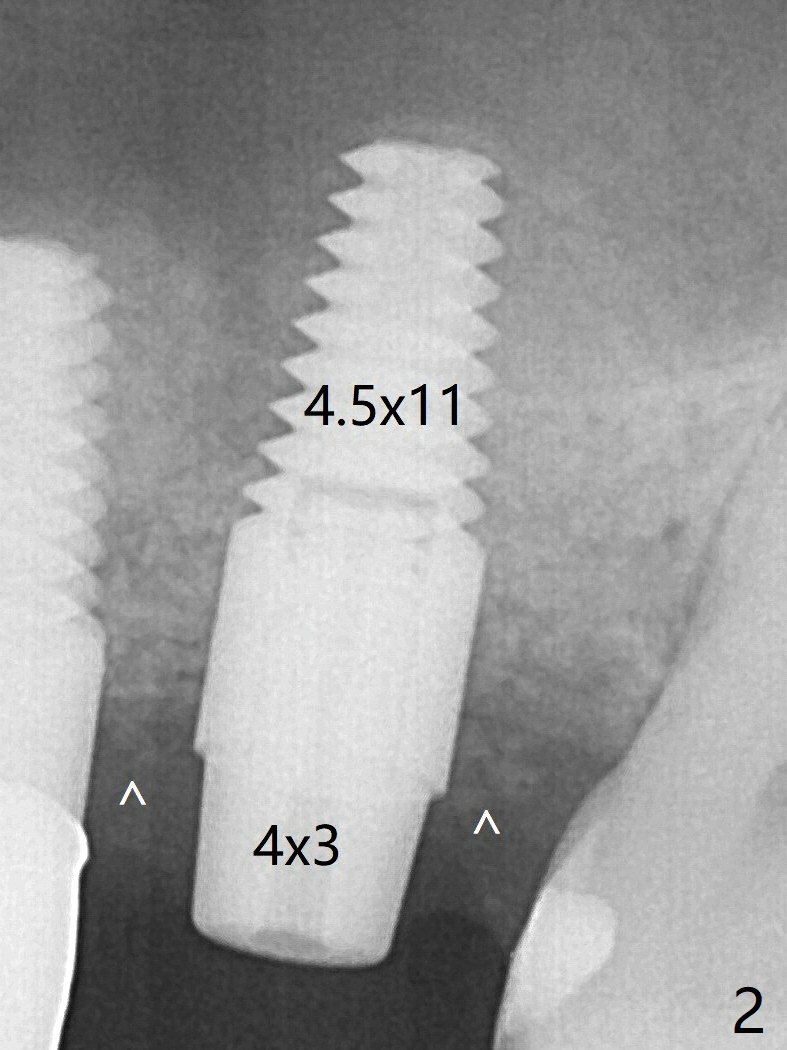

The ridge at #14 seems wide 6 months post implant removal and bone graft (before and after incision).  In fact the palatal bone is low, which was the basis for periimplantitis.  The new osteotomy is not initiated buccal enough.  When a 4.5x14 mm tap is placed (Fig.1), the palatal threads are exposed.  The buccal bone of the osteotomy has to be removed before placement of a 4.5x11 mm with 1 thread exposure palatal (Fig.2).  Periimplantitis at #13 is found intraop (Fig.1 *).  After removal of granulation tissue and use of Titanium brush, allograft is placed at #13 and 14 (Fig.2 ^) and is covered by PRF.  If there is difficulty in restoration due to deep implant placement, it has to be backed up using torque wrench.  The implant is subgingival nearly 3 months postop (Fig.4 ^: gingival margin).